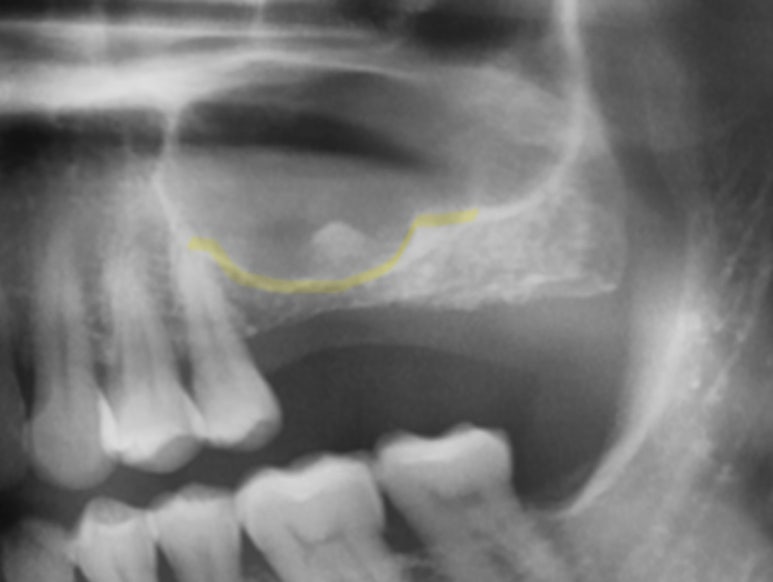

수술 전 사진

위 환자분의 경우도 치아를 발치 후 상악동이 많이 확장되어 어금니쪽 임플란트를 심기 위해서는 상악동 거상술이 필요하신 경우 였답니다. 파노라마 엑스레이상 노란색으로 살짝 표시해 놓은 부분이 상악동과 치조골의 경계면이지요.

얼핏 봐서 대략 3-4mm 정도 밖에 잔존골이 남지 않아 많은 양의 상악동 뼈이식이 요구되는 상황이었답니다.